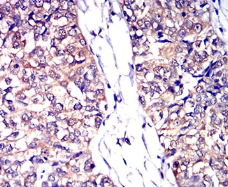

IHC    1/200 - 1/1000